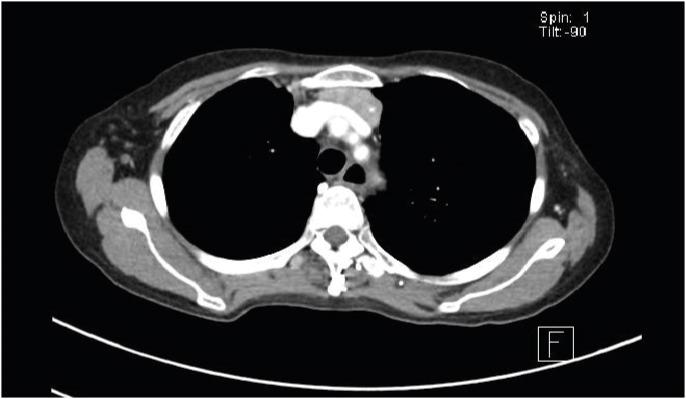

古德综合征(GS)是一种原发性免疫缺陷病(PID),多见于中老年人,伴有胸腺瘤、低丙种球蛋白血症、CD4 T淋巴细胞减少、CD4/CD8 +比值倒置以及T细胞丝裂原增殖反应受损等特征。我们报告一例62岁女性患者,最初表现为乙型肝炎病毒(HBV)再激活导致的急性肝炎,随后因反复肺炎和巨细胞病毒性肠炎反复发作而多次住院。后来发现她患有胸腺瘤和低丙种球蛋白血症,被诊断为GS。虽然T细胞在胸腺瘤免疫病理学中指导B细胞反应的重要性已广为人知,但自然杀伤细胞和CD4 +γδT细胞水平较低也可能是肿瘤发生的免疫监视低下和病毒感染清除能力减弱的原因。因此,HBV再激活后机会性感染与发现胸腺瘤的时间顺序可能反映了作为PID首发表现的免疫监视丧失。